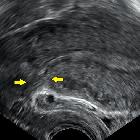

Harnblasenverletzung Kaiserschnitt